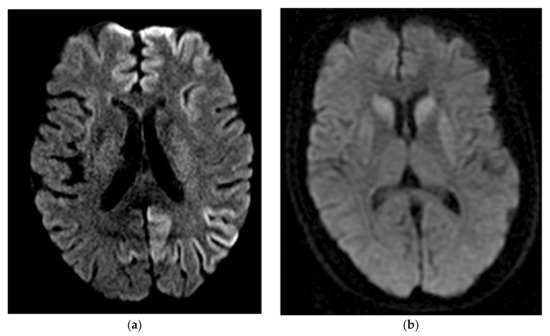

Recently, the development of new MRI criteria has exceeded the sensitivity and specificity of typical CSF biomarkers, approaching equivalence to RT-QuIC (described below). In one study, diffusion MRI was reported to have a sensitivity of 94.7% and specificity of 90%. These results utilized a newly proposed diagnostic criterion requiring a score of at least two on a four-point scale that graded DWI/ADC diffusion restriction on MRI in at least one of the following brain regions, excluding the limbic structures and the cerebellum: cortex of frontal, parietal, occipital, and temporal lobes, caudate, putamen, and thalamus. Diagnostic sensitivity reached 100% when both diffusion MRI and second-generation RT-QuIC were considered together [81]. Though from a single study that requires replication, these results support the improved clinical utility of MRI/DWI in diagnosing prion disease. As sCJD molecular subtypes have neuroanatomic localization patterns, brain MRI can be used to help differentiate sCJD molecular subtypes [97,98], as shown in Figure 1. Diagnostic accuracy of the sCJD molecular subtype can be increased if the PRNP codon 129 polymorphism is known.

Figure 1.

Brain MRI findings in prion disease. (a) Axial DWI imaging showing a widespread cortical restricted diffusion pattern typically found in sCJD MM1; (b) Axial DWI imaging showing restricted diffusion in the bilateral basal ganglia typically seen in sCJD VV2 (ataxic variant).